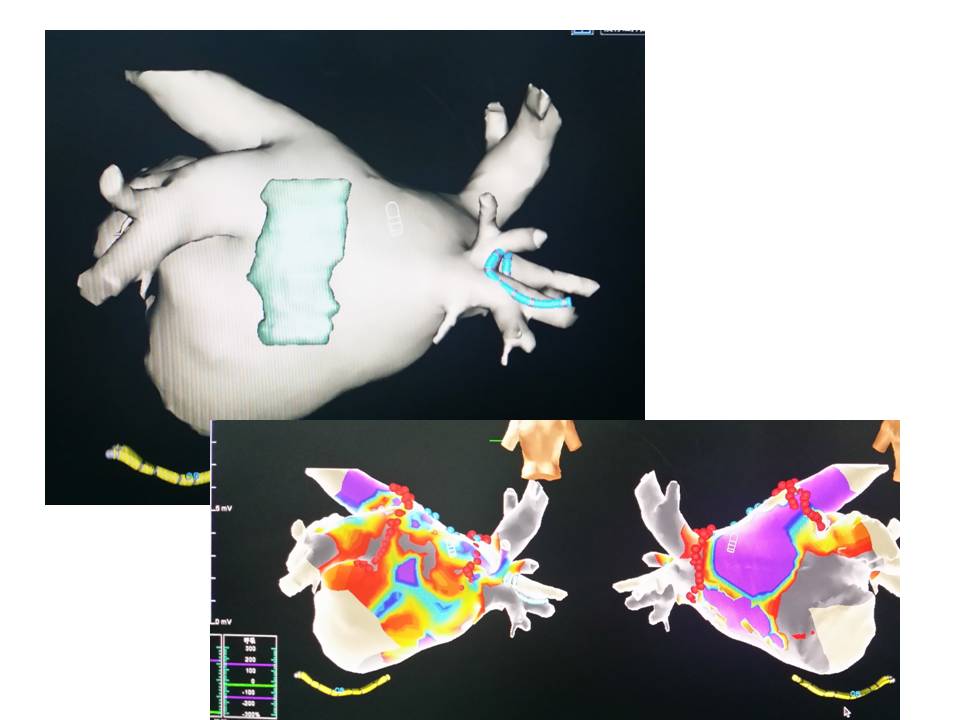

动态融合 实时准确